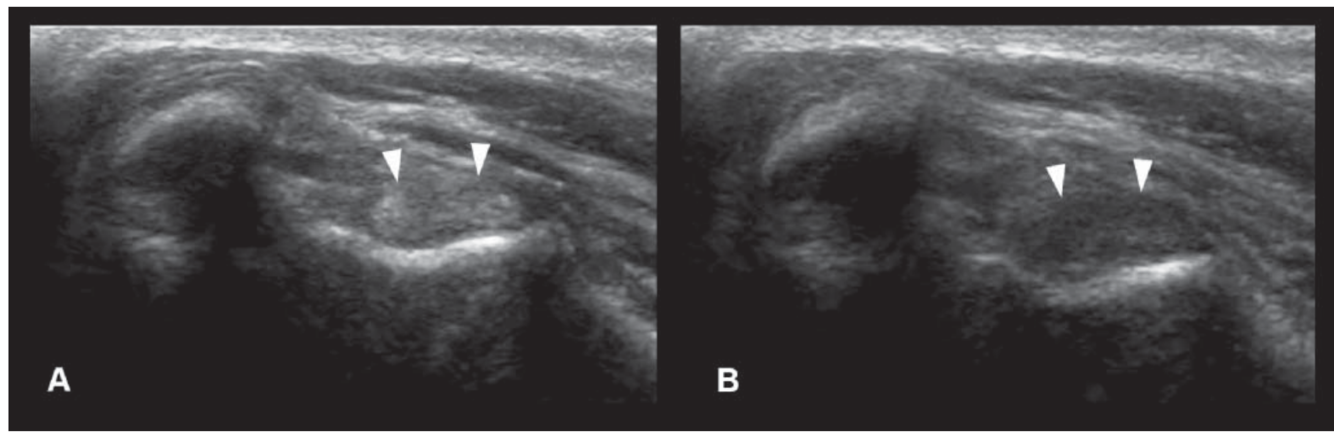

Name this artifact (image on the right)

What is the cause of the artifact? How would you (try to) fix it?

Anisotropy artifact: angle of insonation alters reflective pattern. Normal or hyperchoic when perpendicular; hypoechoic appearance (‘false lesion’) when off angle.

To fix: change the angle of the transducer